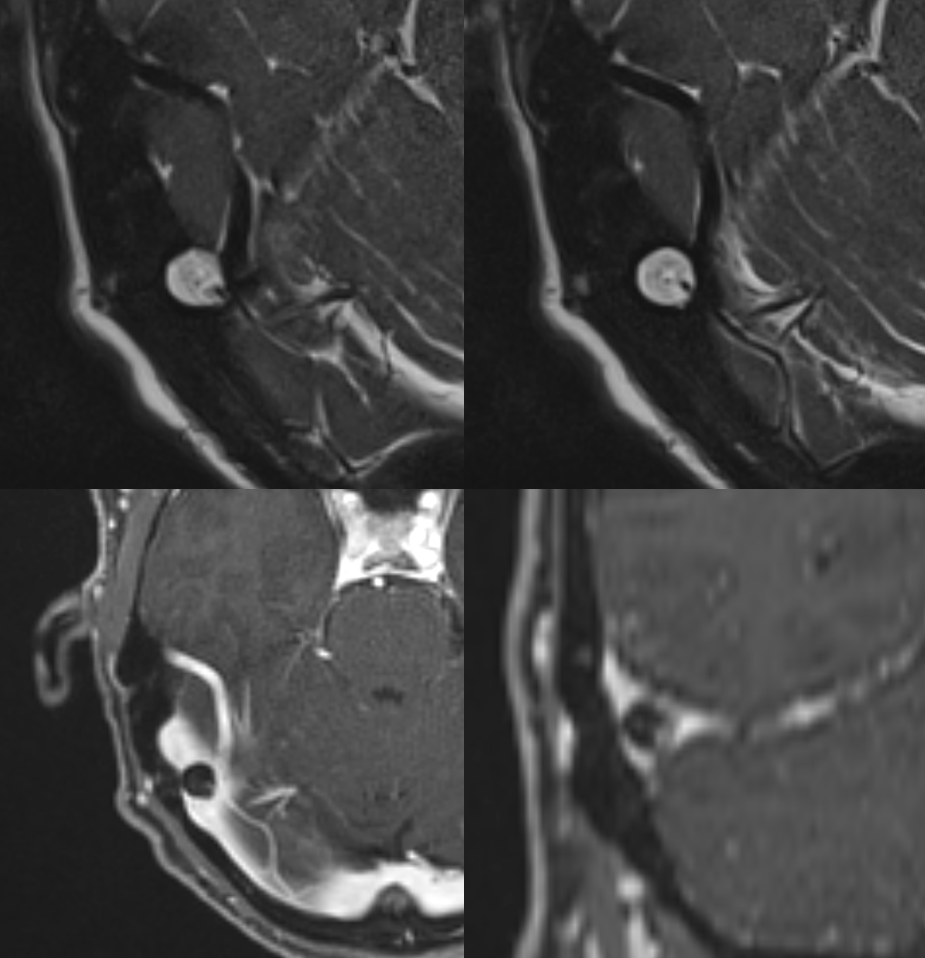

Coronal views — inset is a sagittal view.

Smaller granulation causing venous pulsatile tinnitus — abolished by jugular compression (intrinsic stenosis — granulation narrowing the sinus)